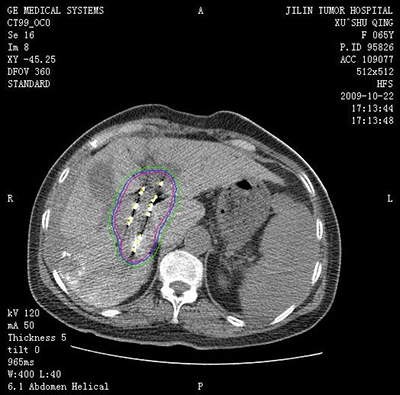

![]() | ![]() |

| (肝癌的消融治疗) | (肺癌的消融治疗) |